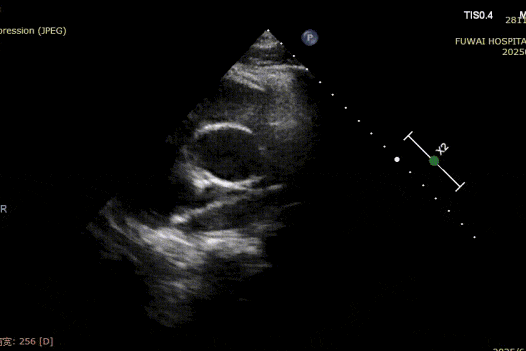

1-day postoperative TTE revealed that the occluder is in good shape without residual shunt (see last figure).

The procedure was guided by TTE following the PAN procedure developed at Fuwai Hospital. This radiation-free, real-time imaging technique offers high-resolution anatomical visualization, ensuring accurate device placement and minimizing complications—particularly valuable in young, reproductive-age patients.